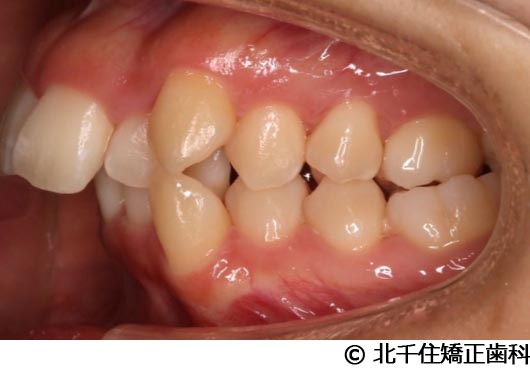

【症例5】上顎前突

- 治療前

- 治療後

- 治療名

- 上顎前突

- 費用

- 1,263,600円(税込)

- 期間

- 2年8ヵ月

- 治療回数

- 32回

- 通院頻度

- 1ヵ月ごと

- 年齢

- 13歳3ヵ月(初診時)

治療内容

-

患者様の症状

主訴:出っ歯

治療方法

骨格性の上顎前突、ヘッドギアを併用して上下顎第一小臼歯4本抜歯してワイヤー矯正。

治療結果

骨格性上顎前突に対し、ヘッドギアおよび抜歯を併用した矯正治療により歯列および咬合関係の調整を行った症例である。

治療後は保定装置を使用し、歯列および咬合の安定維持を目的として定期的な経過観察を行っている。